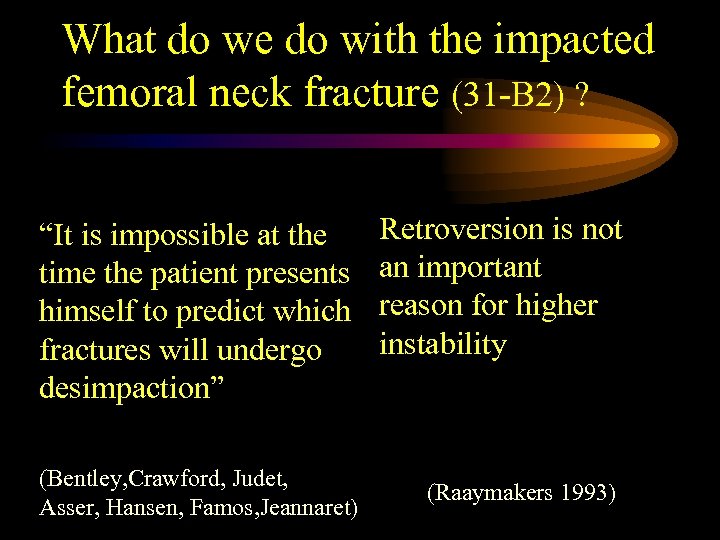

What do we do with the impacted femoral neck fracture (31 -B 2) ? “It is impossible at the time the patient presents himself to predict which fractures will undergo desimpaction” (Bentley, Crawford, Judet, Asser, Hansen, Famos, Jeannaret) Retroversion is not an important reason for higher instability (Raaymakers 1993)

What do we do with the impacted femoral neck fracture (31 -B 2) ? “It is impossible at the time the patient presents himself to predict which fractures will undergo desimpaction” (Bentley, Crawford, Judet, Asser, Hansen, Famos, Jeannaret) Retroversion is not an important reason for higher instability (Raaymakers 1993)